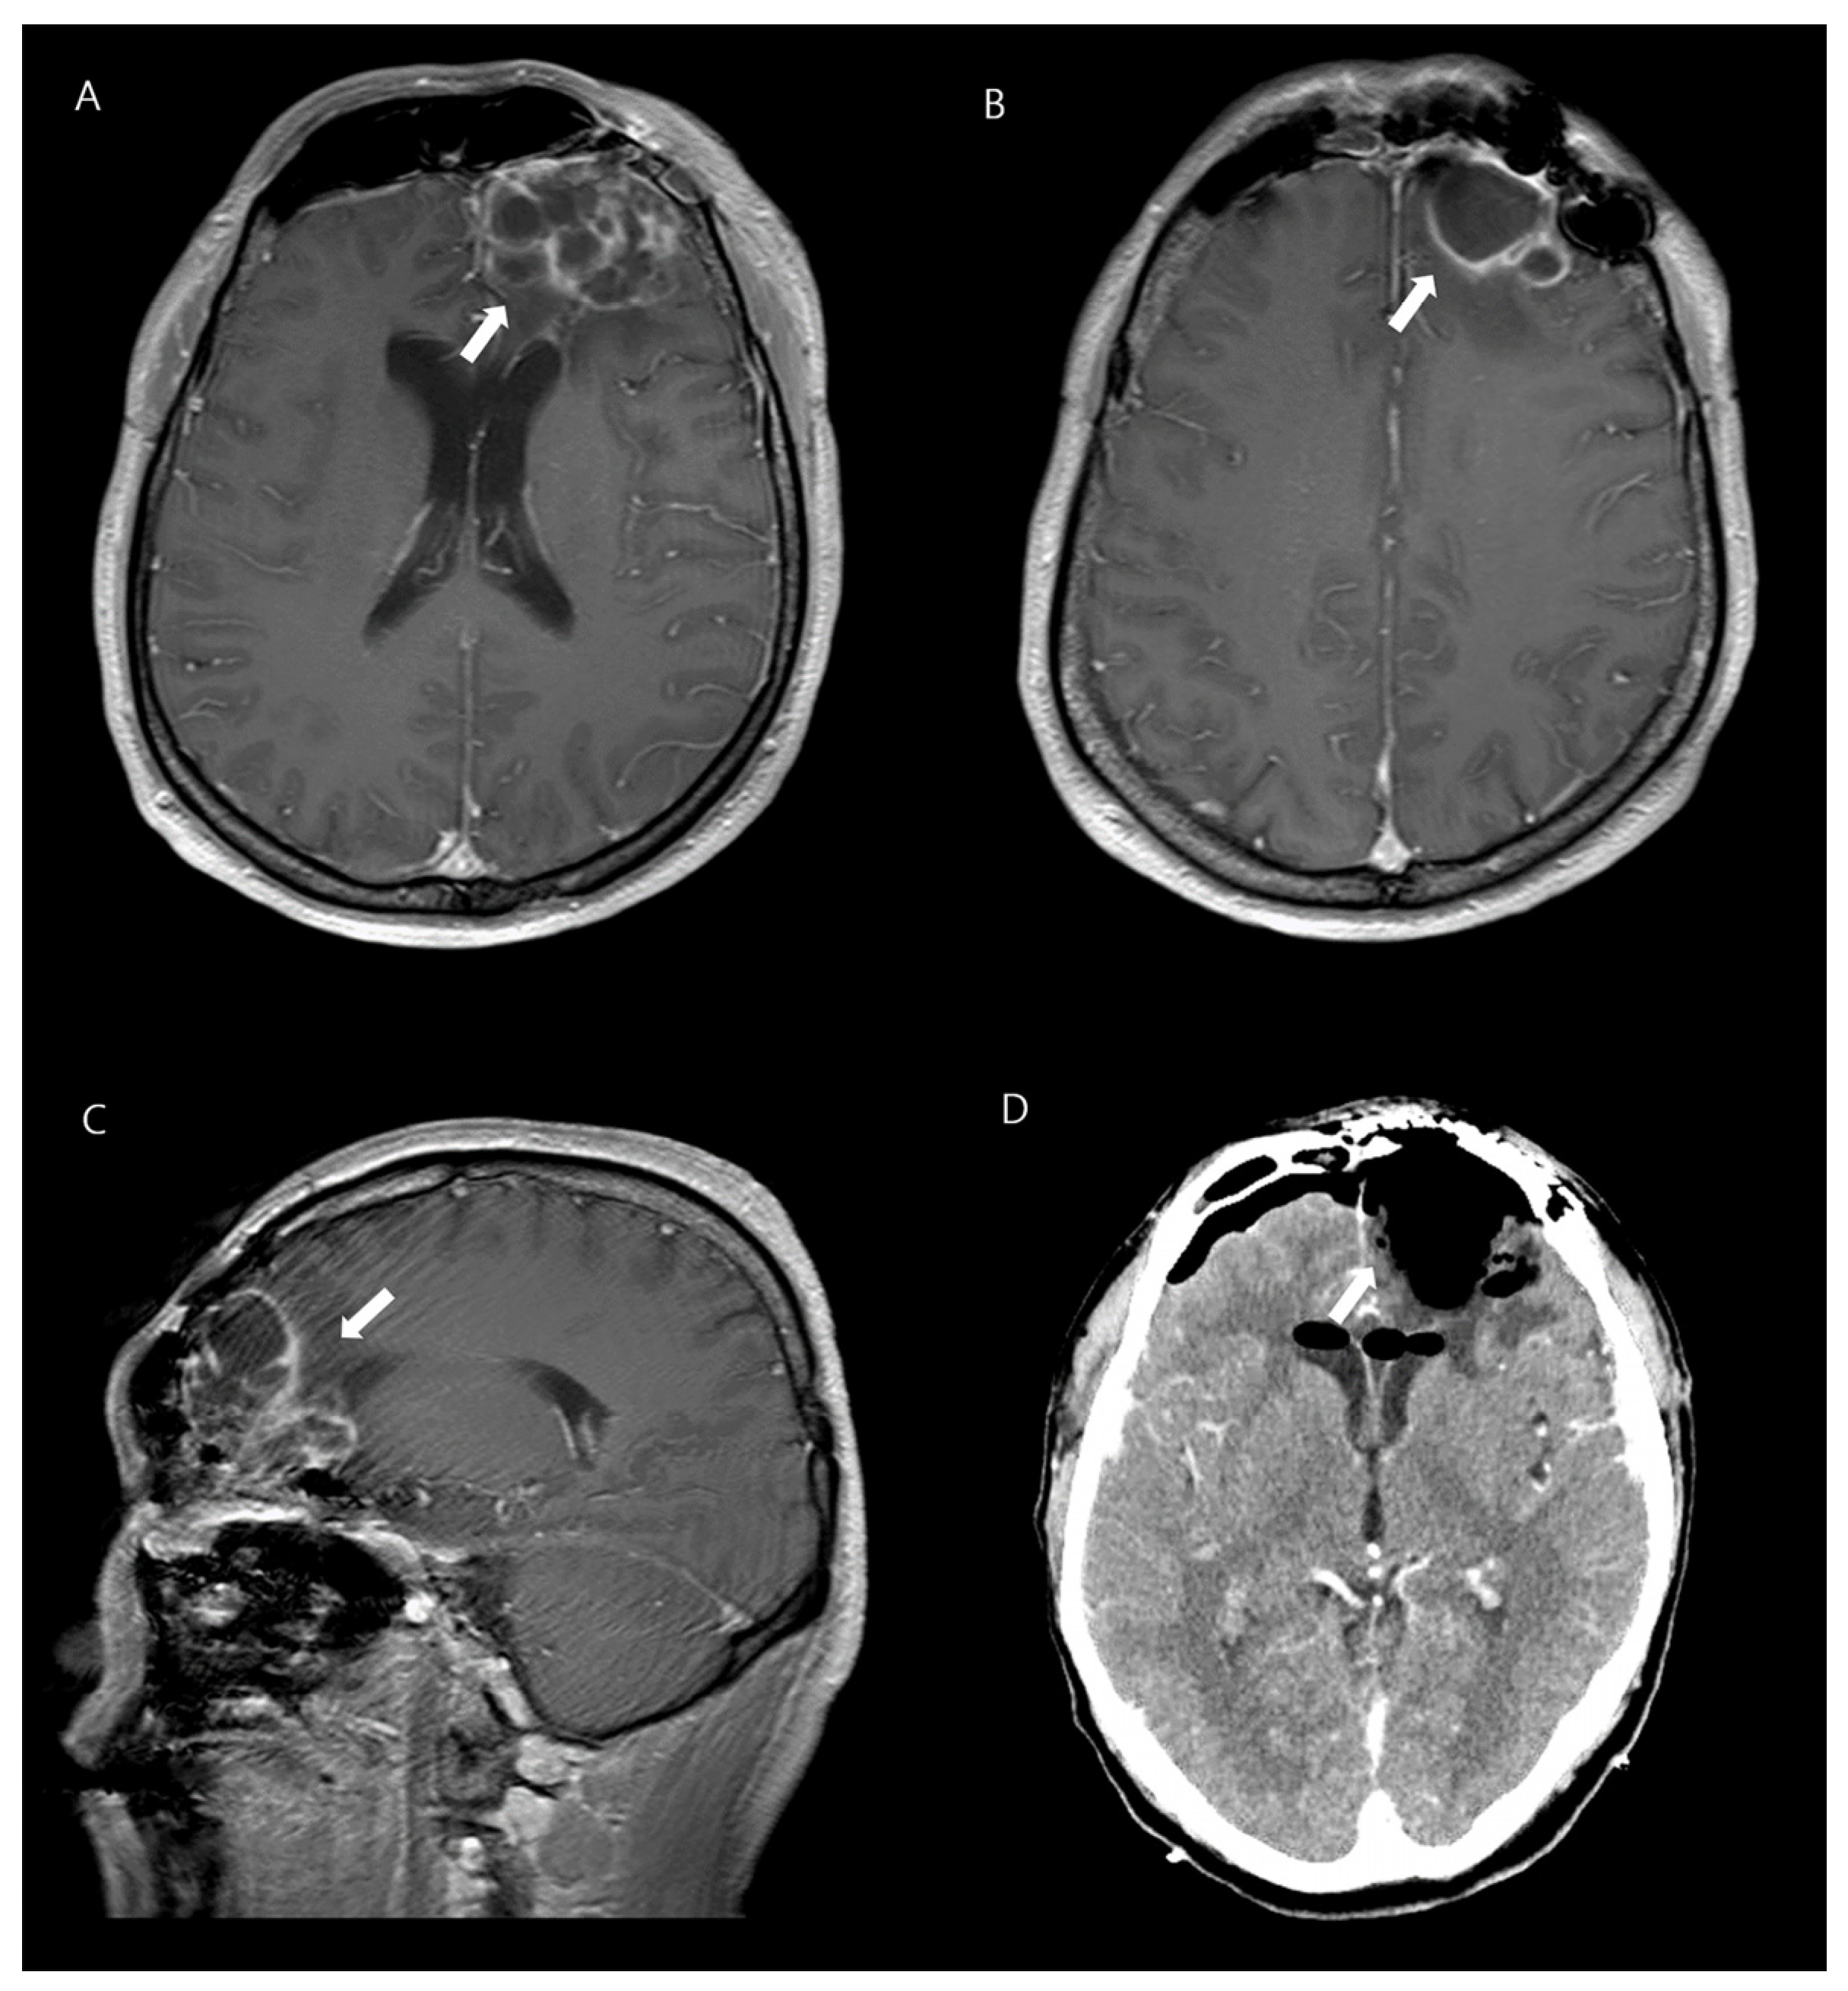

Further investigations, including a lumbar puncture, were performed. The patient’s biochemistry and hematology panel showed normal liver and renal function, as well as an absence of leukocytosis with a normal differential cell count, except for elevated levels of high-sensitivity C-reactive protein (109.4 mg/L) and procalcitonin (1.98 ng/mL). Urinalysis was normal. Analysis of cerebrospinal fluid (CSF) obtained through lumbar puncture showed a cloudy appearance; elevated white blood cell count of 2460/mm3, with a predominance of neutrophils (81%); and abnormal protein and glucose levels (510.7 mg/dL and 5 mg/dL, respectively). The patient’s intracranial pressure was found to be elevated at 190 mmH2O. Gram staining of the CSF did not show any microorganisms and cultures were negative. However, blood cultures showed K. pneumoniae growth. Nasopharyngeal swab culture was taken to identify K. pneumoniae colonization, and it tested positive. A chest X-ray; computed tomography (CT) scan of the chest, abdomen, and pelvis; electrocardiogram; and transthoracic echocardiogram were performed, all of which revealed no abnormalities. However, magnetic resonance imaging (MRI) of his brain revealed a lobulated lesion with rim enhancement, suggestive of abscess, in the left frontal area and craniotomy site, and showed evidence of ventriculitis and empyema in both lateral ventricles (Figure 1).

Figure 1.

A 42-year-old man with K. pneumoniae brain abscesses. Axial contrast-enhanced T1-weighted images (A,B) and sagittal image reveal thin-walled rim-enhancing abscesses in the left frontal lobe (C). Enhanced brain CT shows disappeared lesions after the neurosurgery (D).